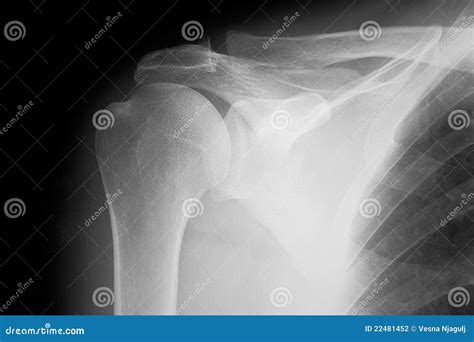

Understanding the significance of a shoulder X-ray normal result is crucial for both medical professionals and patients. A shoulder X-ray is a common diagnostic tool used to evaluate the bones, joints, and surrounding soft tissues of the shoulder. This imaging technique helps identify fractures, dislocations, arthritis, and other abnormalities. However, interpreting a shoulder X-ray normal result requires a thorough understanding of the anatomy and potential pathologies that can affect the shoulder.

A shoulder X-ray is a non-invasive imaging test that uses electromagnetic radiation to produce images of the shoulder joint and surrounding structures. This test is often the first step in diagnosing shoulder pain or injury. The X-ray can reveal fractures, dislocations, arthritis, and other bone abnormalities. However, it may not always show soft tissue injuries, such as tears in the rotator cuff or ligaments.

When a shoulder X-ray normal result is reported, it means that the X-ray images do not show any visible abnormalities in the bones or joints. This can be reassuring for patients experiencing shoulder pain, as it indicates that there are no obvious fractures or dislocations. However, it is important to note that a normal X-ray does not rule out all possible causes of shoulder pain.

• No Visible Fractures: The bones of the shoulder appear intact, with no signs of breaks or cracks.

• No Dislocations: The bones are properly aligned, indicating that there is no dislocation of the shoulder joint.

• No Arthritis: There are no visible signs of bone spurs, joint space narrowing, or other indicators of arthritis.